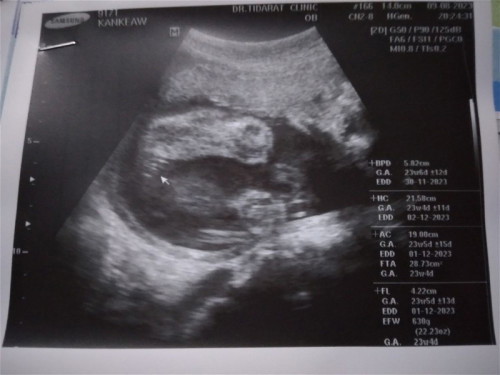

ดูเพศลูก หญิงหรือชายน้อ

ช่วยดูหน่อยค่ะแม่ๆ หญิงหรือชาย 🥰

กลีบๆลูกสาวจ้า